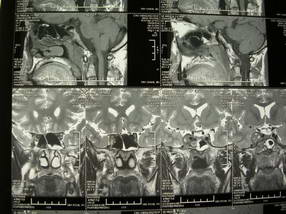

男、30、发现鼻咽部肿瘤侵犯海绵窦,未发现明显淋巴肿。请问国内那家医院治疗鼻咽部肿瘤最好?手术以何种方式为主?病灶可否全部切除?急切期待的大家的帮助。

扫描示鼻咽腔不对称,中度狭窄,右侧咽隐窝消失,局部软组织肿块,鼻咽右侧壁增厚形成肿块,突入鼻咽腔,肿块平扫呈等密度,肿块向深部侵润,右侧翼内外肌受侵,右侧咽旁间隙变窄;向后生长,头长肌界线欠清,向后上生长侵犯同侧颈动脉鞘区。双侧海绵窦增宽,内见软组织影与鼻咽部肿块相连。考虑鼻咽癌。鼻咽癌主要是放射治疗,且效果较好;到当地有治疗设备较大医院治疗即可。

这个病例有点特殊,和常见的鼻咽癌不太一样,以向颅内侵犯为主,骨质破坏区小。鼻咽癌首先要考虑,有没有其他可能?本人不会看mr片,期待有人能讲解,期待病理。

鼻咽部新生物(纤维血管瘤?鼻咽癌?)侵犯右侧中颅窝底及右侧海绵窦;建议必要时活检定性。